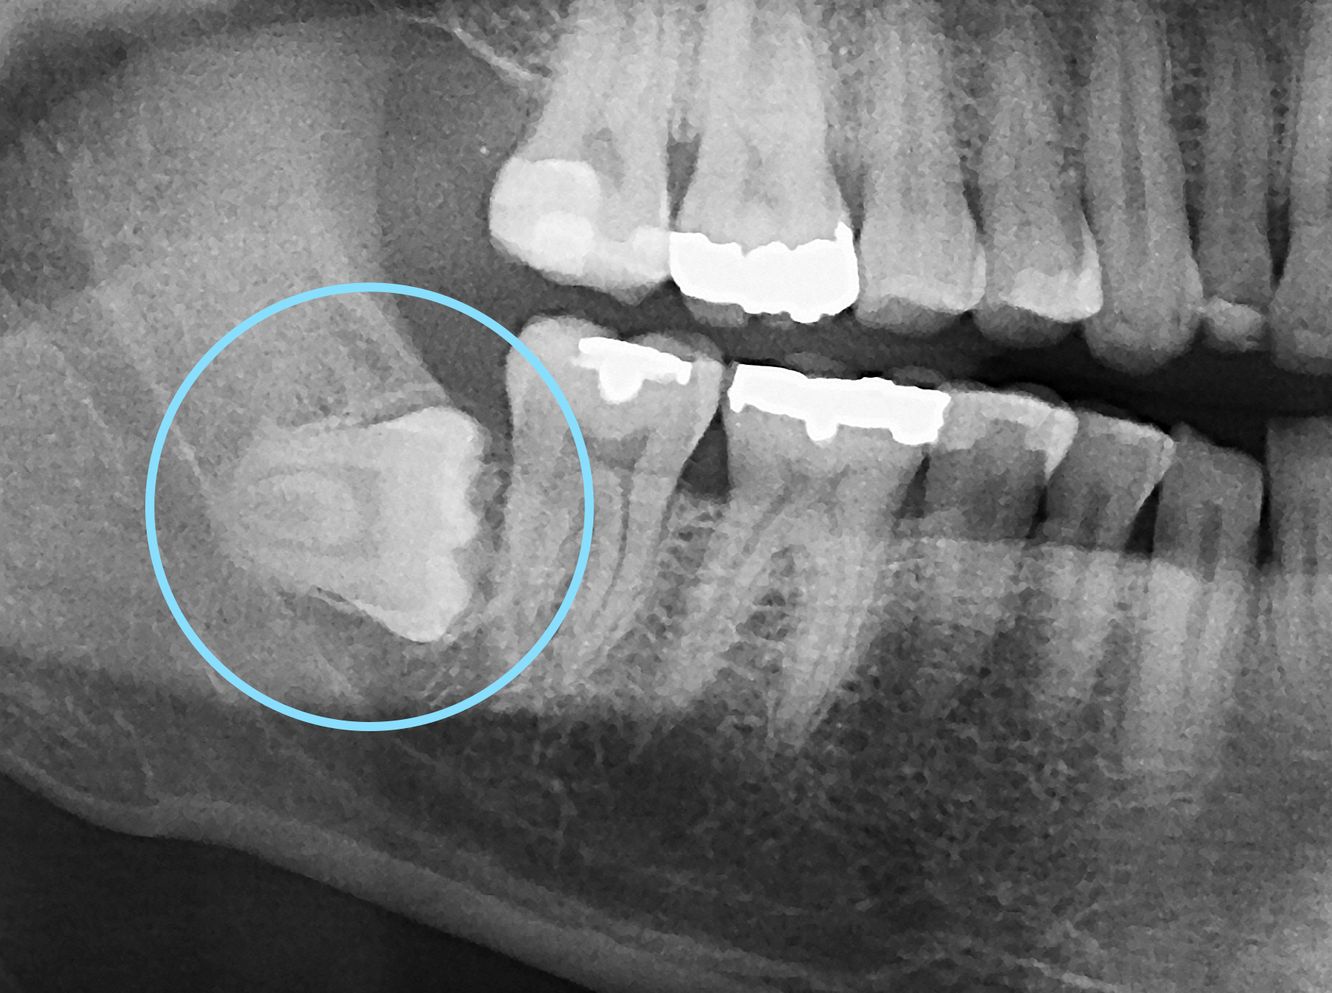

Quelles sont les indications de l'extraction des dents de sagesse

Extraction des dents de sagesse Quand et pourquoi